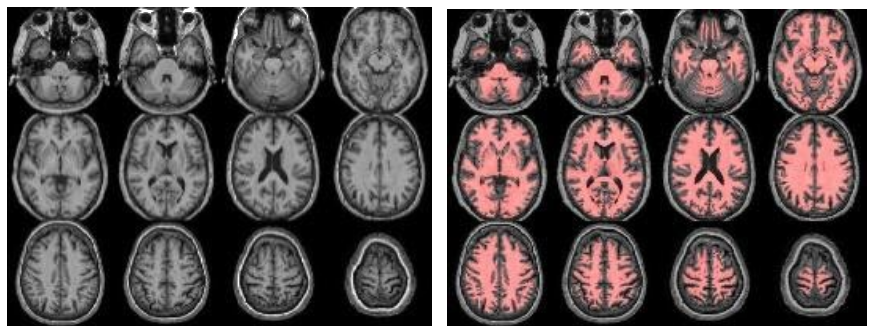

The structural module processes the anatomical (T1-weighted, T1w) images, to provide segmentations/partial volume (PV) maps and for spatial normalization to MNI space. Optionally, if FLAIR images exist, these are used to correct the white matter hyperintensities (WMH) on the T1w images. Check (from left to right):

//Population/T1Check/Tra_Src_rT1_*.jpgfor T1w quality, structural anomalies, normalization to MNI//Population/T1Check/Tra_Reg_rT1_*.jpgsame as previous, but after lesion filling (if FLAIR exists)//Population/T1Check/Tra_Seg_rT1_*.jpgfor T1w segmentation (WM segmentation in red)//Population/TissueVolume/Tissue_volume_*.tsvfor the GM, WM and CSF volumes- Note that all QC images are prefixed with ‘Tra_’ (transversal/axial)/ ‘Cor_’ (coronal) or ‘Sag_’ (sagittal) denoting the plane of the slices.